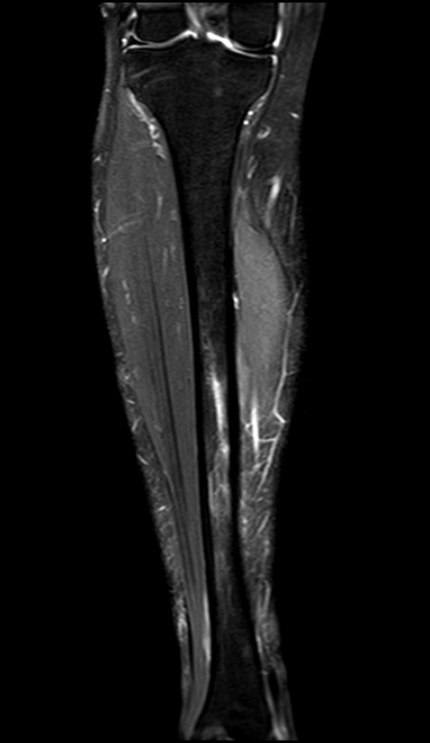

L’IRM (Imagerie par Résonance Magnétique) : C’est l’examen de référence. L’IRM permet de voir l’inflammation à l’intérieur de l’os (l’œdème osseux) et de visualiser la fissure bien avant la radiographie.

IRM Fracture de fatigue du tibia.